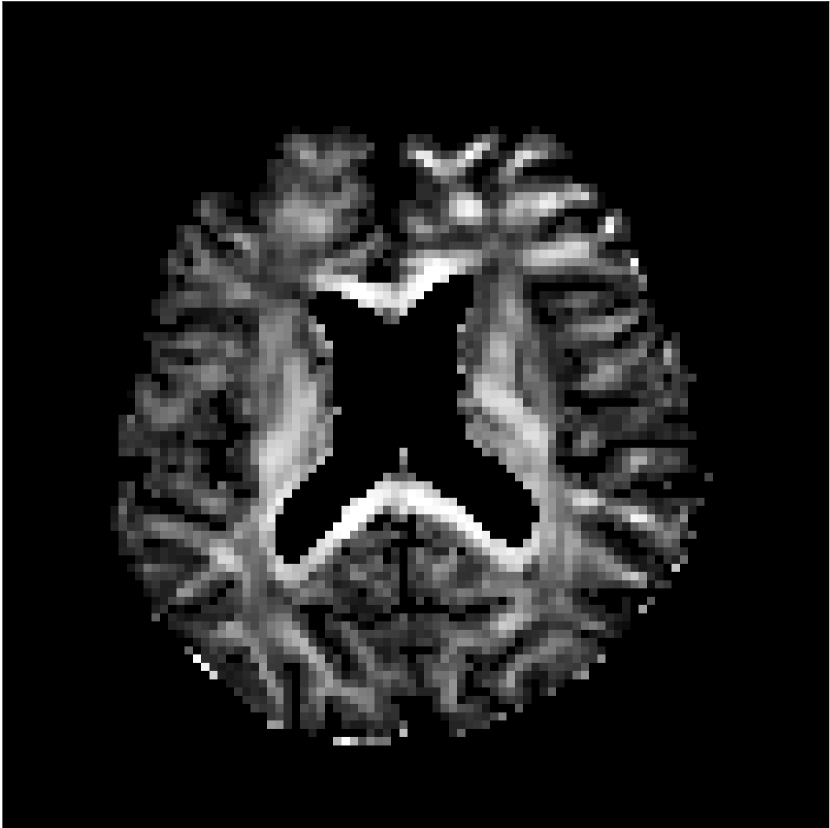

Figure 8 shows examples of non-diffusion-weighted images before and after processing. The raw images (Raw) served as the input for the magnitude deep learning (MCNN) and complex deep learning (CCNN) methods.

Raw

MCNN,

MCNN Resid.,

CCNN,

CCNN Resid.,

No PF

5/8 PF

Both methods remove artifacts, but the MCNN method allows residual rippling artifacts to pass through in the presence of partial Fourier. These rippling artifacts are not present in the CCNN method.